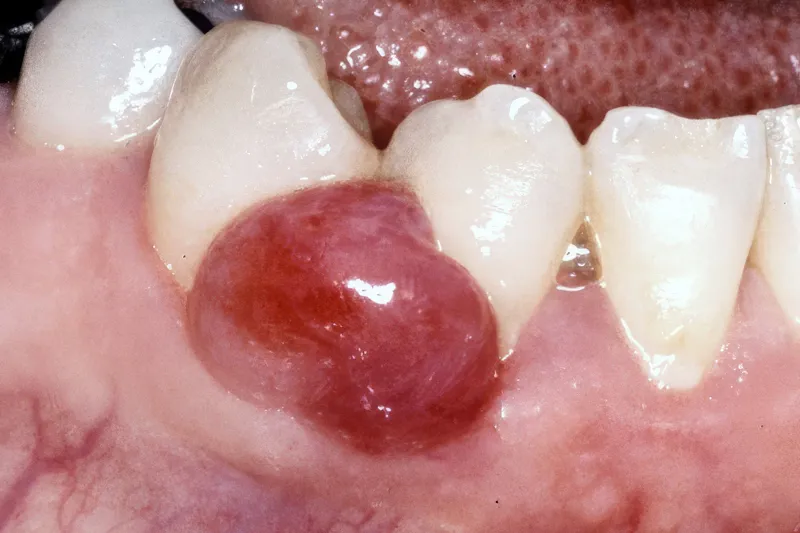

Hævelser i mundslimhinden kan opstå som følge af en væskeansamling (fx spyt, pus og ødem) eller en vævsforøgelse. Vævsforøgelser kan være non-neoplastiske eller neoplastiske. De non-neoplastiske vævsforøgelser er hyppigst forekommende og er ofte reaktive, irritationsbetingede hyperplasier (fx det pyogene granulom eller den fokale fibrøse hyperplasi). De kan også være relateret til generelle sygdomme, medicinindtagelse eller være udviklingsbetingede. Infektion med humant papillomvirus kan resultere i udvikling af papillomer, og mucocele kan opstå som følge af traumatiseret spytkirtelvæv. Ved bl.a. morbus Crohn kan ses hævelser i form af mukosale hyperplasier/folder med granulomatøs inflammation. Gingivale hyperplasier er de mest almindelige medicininducerede hævelser. De neoplastiske vævsforøgelser er karakteriserede ved abnorm og ukontrolleret cellevækst og kan være benigne eller maligne tumorer. Såvel de benigne (fx fibrom) som maligne (fx fibrosarkom) neoplasier forekommer sjældnere, men udgør væsentlige differentialdiagnoser. Det kan undertiden være vanskeligt klinisk at adskille reaktive hyperplasier fra egentlige neoplasier. Det exciderede væv skal derfor altid undersøges histologisk for endelig verifikation af diagnosen. De forskellige mundslimhindetumorer kan også være vanskelige at adskille klinisk. En biopsi vil således være påkrævet og selvsagt afgørende for den videre behandling. Det er vigtigt for tandlæger at have kendskab til de forskellige typer af mundslimhindehævelser for at kunne stille relevante kliniske tentative diagnoser og vide, hvornår der er grundlag for biopsi og videre henvisning til specialtandlæge eller speciallæge. I nærværende artikel gennemgås de mest almindelige mundslimhindehævelser og relevante differentialdiagnostiske overvejelser.